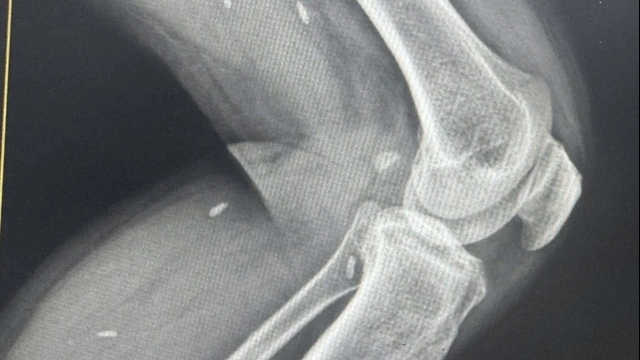

Tại đây, người bệnh được chẩn đoán: Nhồi máu cơ tim cấp ST chênh lên (STEMI) giờ thứ 4 - một cấp cứu tim mạch với nguy cơ tử vong cao nếu không được xử trí kịp thời. Bệnh nhân được chụp mạch vành qua da cấp cứu, phát hiện tắc hoàn toàn động mạch liên thất trước (LAD) và tiến hành can thiệp đặt stent động mạch vành, dòng chảy sau can thiệp tốt.

Sau can thiệp, người bệnh được chuyển về bệnh phòng tiếp tục theo dõi sát. Trong lúc đang được theo dõi sau can thiệp, bệnh nhân đột ngột xuất hiện mất ý thức, trên máy theo dõi là hình ảnh rung thất - Rối loạn nhịp nguy kịch gây ngừng tuần hoàn. Người bệnh được hồi sức tim phổi, ép tim ngoài lồng ngực, sốc điện nhiều lần với tổng thời gian ngừng tim phải tiến hành cấp cứu ngừng tuần hoàn 60 phút.